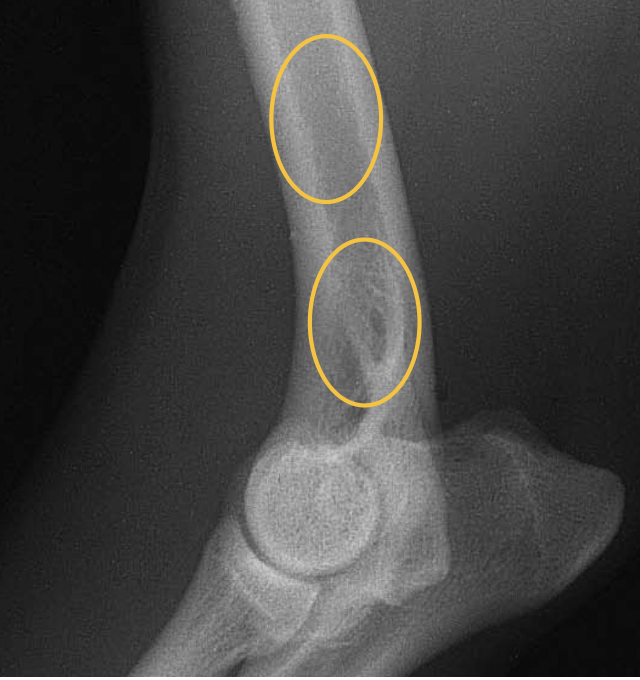

where in the ulna is there a slight increase in opacity?

at the proximal extremity of the medullary cavity

where is the caudal ulnar cortex thicker?

in the proximal third of the diaphysis